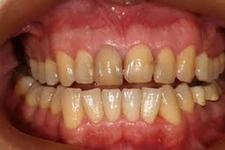

Diş ekimi, kaybedilen dişlerin yerine yapay dişlerin yerleştirilmesi işlemidir. Bu işlem, hem estetik hem de fonksiyonel açıdan birçok avantaj sunmaktadır. Diş ekimi, günümüzde diş hekimliği alanında en yaygın kullanılan yöntemlerden biri haline gelmiştir. Bu makalede, diş ekiminin faydaları detaylı bir şekilde ele alınacaktır. Diş Ekimi Nedir?Diş ekimi, kaybedilen dişlerin yerine cerrahi bir işlemle titanyum veya benzeri malzemelerden yapılan yapay diş köklerinin yerleştirilmesini içeren bir tedavi yöntemidir. Bu işlem, diş kaybının neden olduğu estetik kaygıları gidermenin yanı sıra, çiğneme fonksiyonunu da yeniden kazandırmaktadır. Diş Ekiminin Estetik FaydalarıDiş ekimi, hastaların gülümseme estetiğini önemli ölçüde iyileştirmektedir. Aşağıdaki avantajlar estetik açıdan dikkate değerdir:

Diş Ekiminin Fonksiyonel FaydalarıDiş ekiminin fonksiyonel avantajları da oldukça önemlidir. Bu avantajlar şunlardır:

Diş Ekiminin Sağlığa FaydalarıDiş ekimi, sadece estetik ve fonksiyonel avantajlar sunmakla kalmaz, aynı zamanda sağlık açısından da faydalar sağlar: